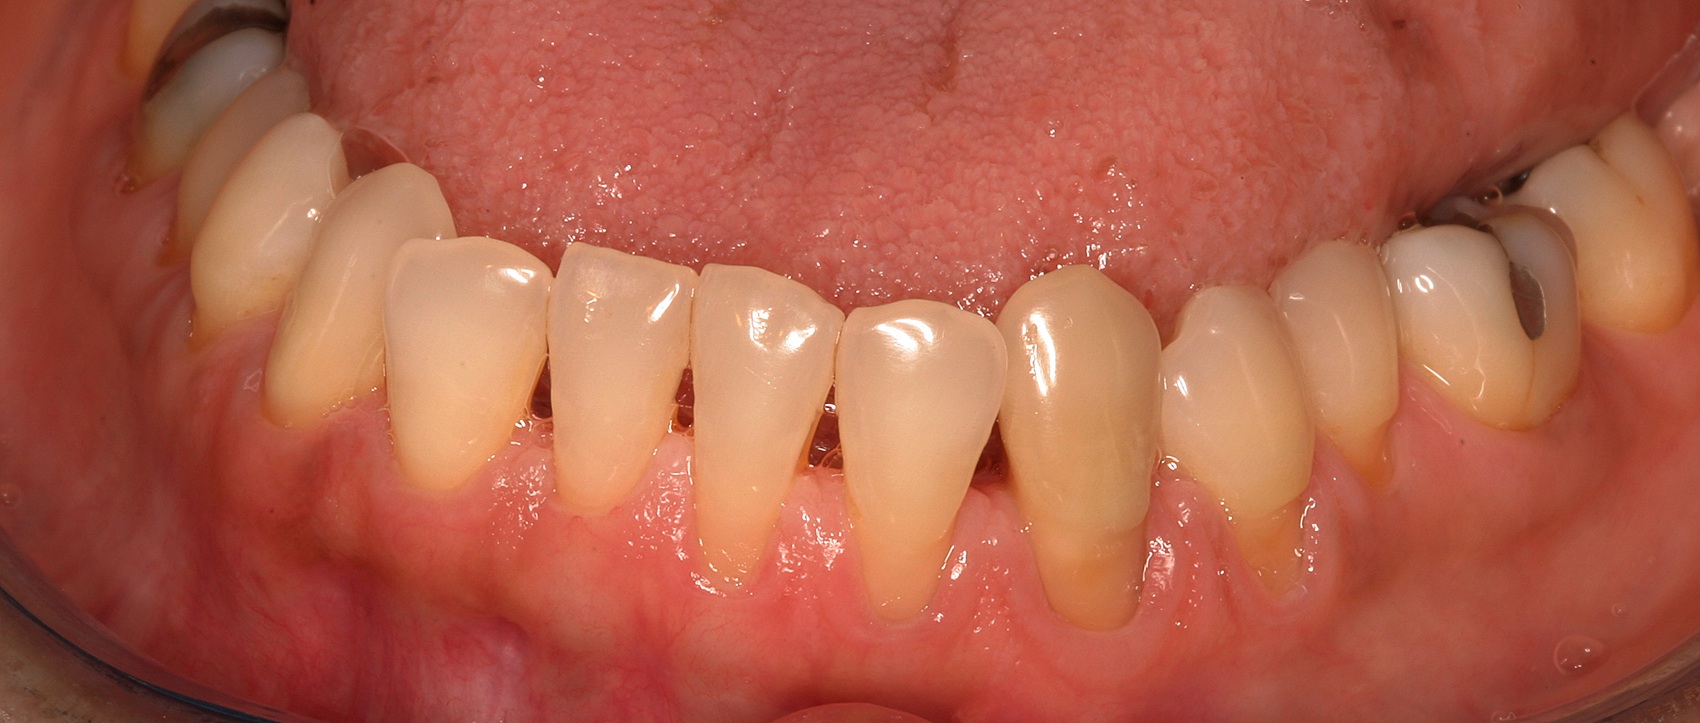

The 2.5-year postoperative photograph.

Fig. 10

In the coming decades, restorative treatment for aging patients who experience facial growth with recession and erosion below the cemento-enamel junction because of tooth movement may be especially challenging. However, if dentists can employ the tenets of regeneration using autogenous tissues or a cellular dermal matrix combined with enamel matrix derivatives as a regulatory protein, they may predictably achieve large amounts of root coverage with thickened periodontium. This would not eliminate the need for restorative dentistry, but would enable restorative dentists to place restorations that are supragingival and are easily accessible for the patient and the therapist during maintenance (Figure 8 through Figure 10).